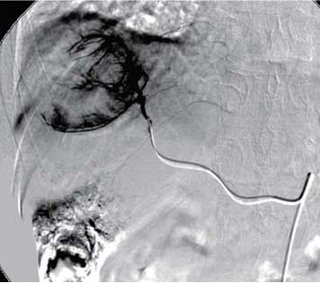

肝动脉栓塞化疗术

肝动脉栓塞化疗术(transcatheter arterial chemoembolizationTACE)

为微创的介入治疗手段,主要经肝股或桡动脉插管将抗癌药物及栓塞剂注入肝脏肿瘤的供血肝动脉分支的一种局部化疗及栓塞治疗方法,它是非开腹手术治疗肝癌的首选方法,其疗效已得到肯定有效的提高了肝癌患者的生活质量,延长了患者的生存期。该治疗优点较多,创伤小、疗效好、副作用少、花费低,为晚期肝癌综合治疗重要手段之一,部分患者可以获得二期手术切除的机会。